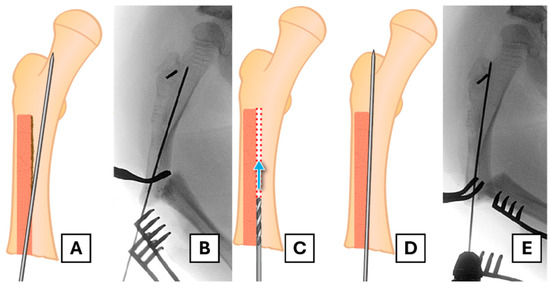

4.4. Revision Rod Placement

Once successful removal is completed, the placement of a revised FD rod is undertaken in a standard open osteotomy fashion. There may be a pseudocortex present in the proximal segment, dividing the previous rod tract from the desired line of exit through the greater trochanter. Accurate placement of the guidewire can be challenging, as it tends to follow the previously created channel and may be pushed medially by the sclerotic edge (Figure 5A,B). To solve this problem, curettage or drilling may be necessary to allow the guidewire to follow the appropriate path through the proximal segment to its exit point. We used a 2 mm drill bit to create a pathway in the desired line, creating access for the guidewire (Figure 5C–E).

Figure 5. Establishing the correct path for the revision rod. (A,B) Illustration and corresponding radiograph showing the guidewire’s trajectory being deflected medially by the sclerotic pseudocortex of the old rod tract. (C) A drill is used to create a new pathway through the blocking bone. (D,E) Illustration and radiograph confirming the correct trajectory of the guidewire towards the greater trochanter apex.